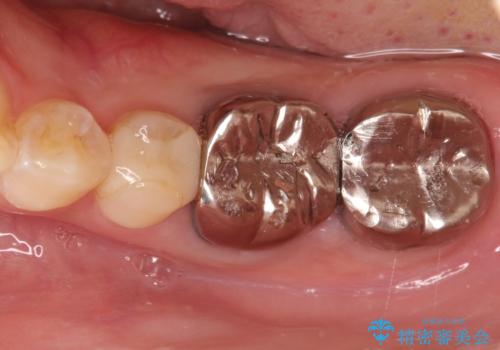

【メタルフリー】オールセラミッククラウン

- 金属冠を白くしたいことを主訴に来院されました。

オールセラミッククラウン(st)にて修復しております。